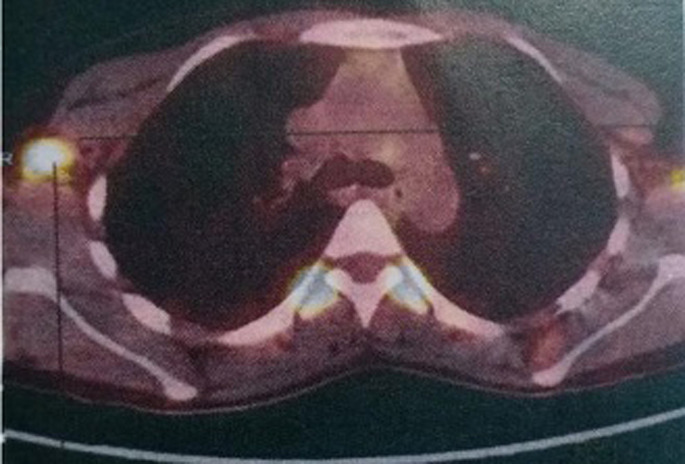

乳腺叶状瘤(PT)是罕见的。它们可以是良性的、边缘性的或恶性的。恶性形式占20-30%的PTs,远处转移在10-26%的病例。化疗是转移性叶状瘤(mpt)的主要治疗手段之一。我们在此报告2015年1月至2017年12月在卡萨布兰卡穆罕默德六世癌症治疗中心治疗的四例乳房mpt病例。患者的平均年龄为25 ~ 45岁。在大多数病例中,发现的方式是由于出现了一个巨大的乳房肿块,所有患者的组织学诊断都是基于乳房切除术标本的检查。3例有肺转移,2例有腋窝淋巴结转移,2例有骨转移,只有1例有肝转移。所有患者均接受化疗。采用阿霉素单药治疗和阿霉素异环磷酰胺(AI)。只有一名患者有非常好的结果,在3个AI方案后放射学完全缓解。乳房mpt预后不良。全身性化疗的作用还有待确定,特别是目前还没有关于最佳化疗方案的数据。

Phyllodes tumors (PT) of the breast are rare. They can be benign, borderline or malignant. Malignant forms account for 20-30% of PTs, with distant metastases in 10-26% of cases. Chemotherapy is one of the main therapeutic weapons for metastatic phyllodes tumors (MPTs). We here report four cases of MPTs of the breast managed at The Mohammed VI Center For Cancers Treatment in Casablanca from January 2015 to December 2017. The average age of patients ranged from 25 to 45 years. The mode of revelation was represented, in the majority of cases, by the occurrence of a huge breast mass and in all patients the histological diagnosis was based on the examination of mastectomy specimen. Three patients had lung metastases, two had axillary lymph-node metastases, two had bone metastases and only one had liver metastases. All patients received chemotherapy. Doxorubicin monotherapy and doxorubicin-ifosfamide (AI) were used. Only one patient had a very favorable outcome, with radiologic complete response after 3 AI regimens. MPTs of the breast have a poor prognosis. The role of systemic chemotherapy is to be defined, especially since there are no data available on optimal chemotherapy regimen.